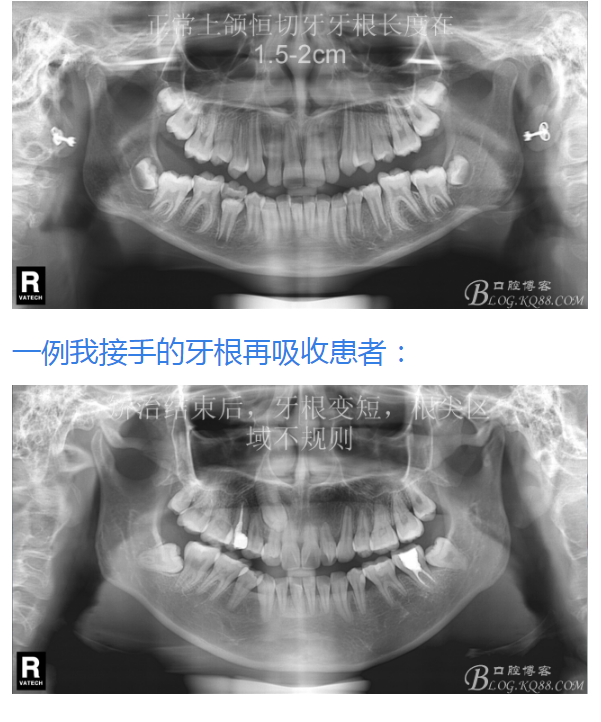

有15%的人在正畸治療前就已經(jīng)發(fā)生牙根吸收,這與激素失衡和飲食缺乏有關。正畸治療后12個月,牙根再吸收的發(fā)生率增加到73%,有25%的正畸治療患者根尖吸收超過2mm,約5%的人發(fā)生超過5mm的嚴重吸收。

大多數(shù)研究認同牙根再吸收的嚴重性與正畸治療的持續(xù)時間、力量大小相關。臨床醫(yī)師應該采用輕力、高效的矯治手段進行正畸治療,并在正畸治療前、中、后進行X線檢查對比,觀察牙根再吸收的發(fā)生情況。研究發(fā)現(xiàn):間斷治療的患者其牙根再吸收量明顯少于那些持續(xù)治療的患者。應用力的中斷有助于已破壞的牙周組織重建并減少牙根的進一步縮短。